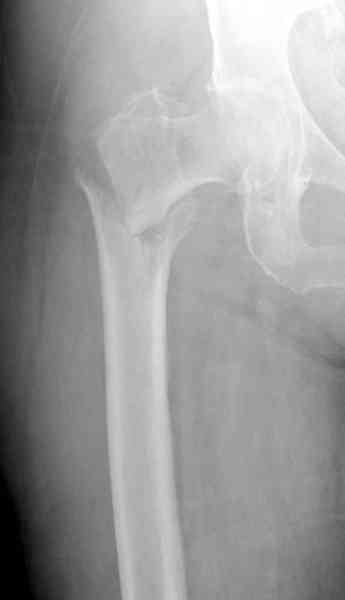

Александр Николаевич, как не прискорбно, я практически заканчивал эту операцию.

Изначально у оперируещего хирурга были только теоретичесике представления о ЗИМО с блокированием, планировался компрессионно-динамический остеосинтез стержнем S2 (Stryker).

Во время операции ни стол ортопедический,ни ДРУ не применялось (думалось, что сделают все на руках!)

Изначально была выбрана не правильная точка введения стержня, в связи с чем в конце, я подчеркну, в конце операции произошло из-за напряжения между прокимальным концом канала бедра и стержнем разрушение в/3 бедра.

Проволока наложена потому, что при введении штифта не прошли эту зону римером и произошли сколы на концах отломков.

Под ЭОП во время операции такого смещения не было. Мы бы конечно не отпустили этого больного с такой картиной (сами бы что-то сделали или к вам отпр).

Почему не сделали R-gr? Все банально для таких больниц как наша - не работал R-аппарат в течении 3х недель.(я сам увидел эти снимки у вас)

В общем, сделали. См. приложение.

Длина и из-за этого ось получились не совсем такие, как хотелось бы, все-таки срок после той операции уже 6 недель. Может быть, стоило провести дистракцию аппаратом неделю-другую. Заранее спасибо за комментарии и критику.